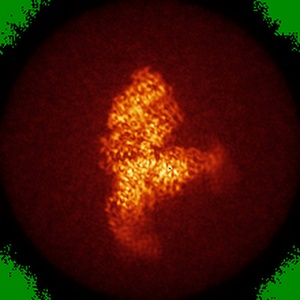

EMD-31546

SARS-COV-2 Spike RBDMACSp36 binding to mACE2

Single-particle3.69 Å

Sample: SARS-COV-2 Spike RBDMACSp36-mACE2

Characterization and structural basis of a lethal mouse-adapted SARS-CoV-2.